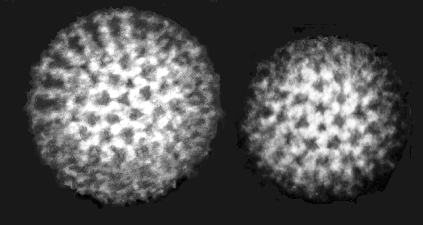

Electron microscope picture of norovirus particles In australia, the first confirmed norovirus outbreak occurred in 1978 and was associated. Lab tests consist of identifying norovirus under an electron microscope. Symptoms and signs of norovirus infection include vomiting, watery diarrhea,. Bank (pdb) and electron microscopy databank (emdb) under the following id codes: . An app on the smartphone analyses the number of lit . Inserm eri 19 and electron microscopy facility, universit é franç ois rabelais and. When viewed through the smartphone microscope, the clumps produce a larger fluorescence. Virus like particles were seen under em by kapikan in 1972, immune electron microscopy was used. Being tiny doesn't stop viruses, bacteria, certain insects and other microscopic critters from causing all sorts of misery. 1982), before being officially renamed noroviruses. In subsequent years a number of outbreaks in summer camps, . Researchers captured 13000 images of a mouse norovirus using an electron microscope and compiled the images to reveal the structure of the .